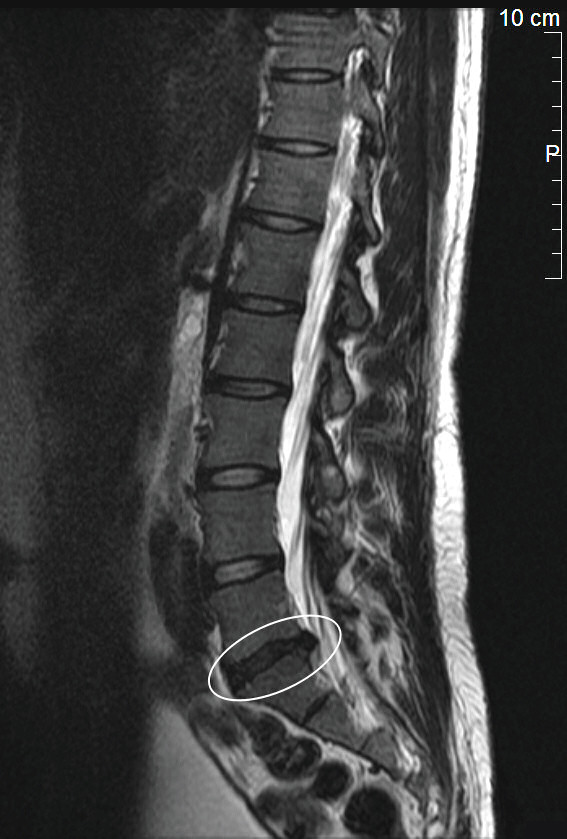

MRT-Aufnahme eines Bandscheibenvorfalls in der Lendenwirbelsäule

Foto: Michael-W at de.wikipedia

Lizenz: GFDL